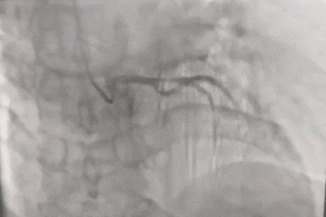

62岁的李先生(化名)1个月前心前区会不时出现胸闷、胸痛等症状,运动、劳累后更易发作,每次发作持续时间3—5分钟,休息或含服速效救心丸后可缓解。李先生在我院心内科五病区住院后,第一时间接受了冠脉造影检查,结果显示前降支开口有一节段严重堵塞,狭窄程度约90%

冠脉造影所示